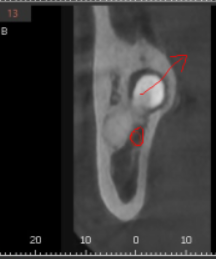

3D-CT를 통해 사랑니와 신경이 근접해 있는 정도

어떻게 발치할 것인가

직접 그리면서 보여드렸죠.

화살표 방향으로 뽑아낼꺼다...

저희 계획중 일부입니다.

신경과 근접해 있기 때문에

최대한 조심스럽게

치아를 조각내 문제없이

깨끗하게 뽑아드렸습니다.